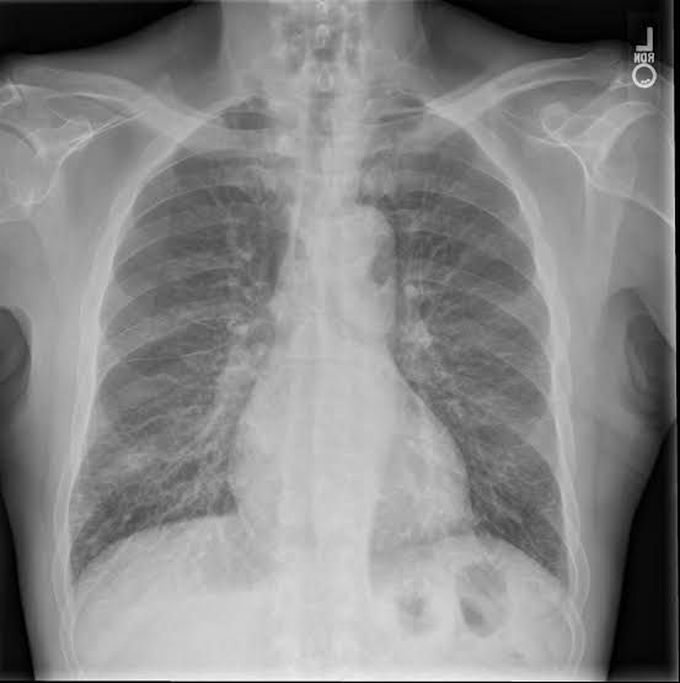

Kerley lines are a sign seen on chest radiographs with interstitial pulmonary edema. They are thin linear pulmonary opacities caused by fluid or cellular infiltration into the interstitium of the lungs. They are named after Irish neurologist and radiologist Peter Kerley.